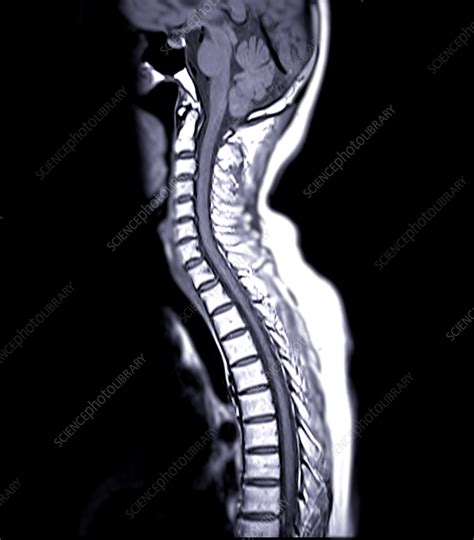

Cervical Spondylosis Mri Scan MRI Images Of Cervical Spine Diseases is a high-quality image in the Rp collection, available at 1300 × 1099 pixels resolution — ideal for both digital and print use.

Understand what to expect during an MRI of the cervical spine. This guide explains how this diagnostic imaging procedure detects neck pain, herniated discs, and nerve compression. Learn why doctors order this non-invasive scan to evaluate spinal cord health and pinpoint underlying conditions for effective treatment planning. Improve your spine care knowledge with our comprehensive overview.

TitleCervical Spondylosis Mri Scan MRI Images Of Cervical Spine Diseases